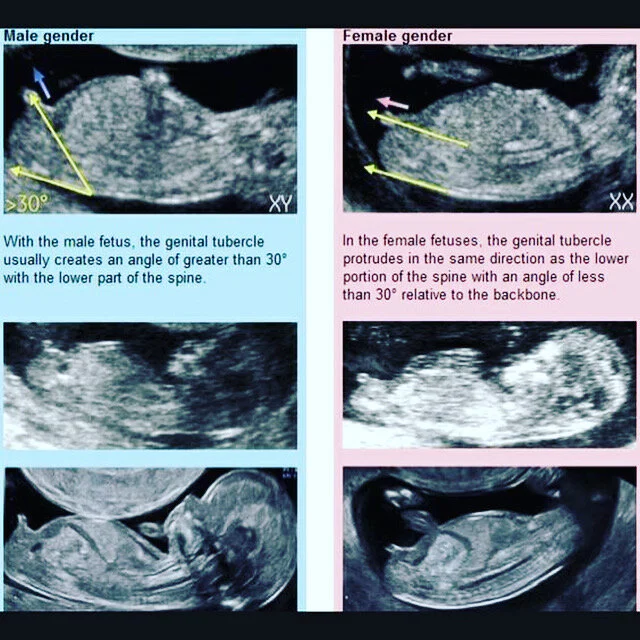

Before the tenth week of pregnancy the genital tubercle looks alike in boy and girl fetuses. But mistakes can be made when determining gender because it. The latest research however suggests we can learn the gender months earlier during the ultrasound for the first trimester screen which is performed sometime between 11 weeks 0 days to 13 weeks 6 days of gestation. If the developing placenta is on moms left side then its more likely a girl. The more body tissue the ultrasound waves must travel through the fuzzier the images may be. Latest 11 Weeks Pregnant Ultrasound Gender Prediction Pin On My Pregnancy Baby 1.

From 11 weeks gestation on we can also add the Nub and Skull theories to increase the accuracy of the prediction. By Tilly1 December 4 2014 in Ultrasound Gender Prediction. Latest 11 Weeks Pregnant Ultrasound Gender Prediction Pin On My Pregnancy Baby 1. I have been fooled too many times by 11 week nubs. This study has demonstrated that the 1113 6 weeks ultrasound scan achieved an accuracy rate of 918 in correctly determining fetal gender in utero for those cases where a determination of gender. The accuracy of nub theory is the highest in or after the 12th week of gestation and sex prediction before 12 weeks is not encouraged.